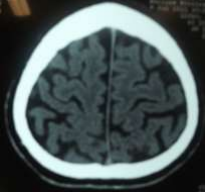

Radiology

Fig 1,2,3,4,5,6,7,8,9,10,11,12,13,14,15

Thirty eight out of Eighty-two patients were treated conservatively and were studied (25 men; 13 females, mean age, 64.8 years). The average thickness of the hematoma was 18 mm, the mean midline shift was 4.7 mm, and the average attenuation value of bleed on computed tomography scan was 33.5. Thirty-eight were treated successfully with steroid treatment, whereas 44 patients required surgery. The female gender, less midline shift, less density (Hounsfield units) was noted to be associated with successful medical treatment. We propose a grading based on the total score given to the midline shift and density.